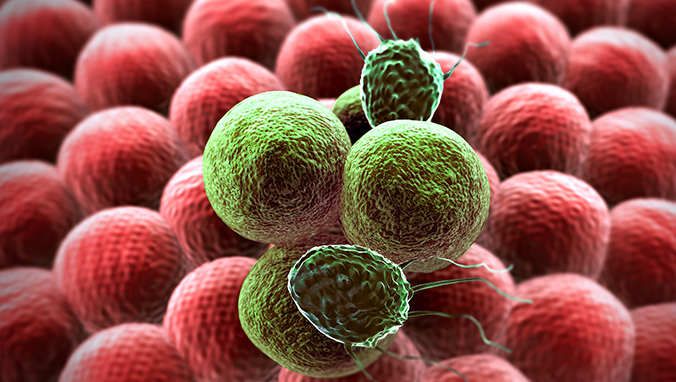

这种病毒竟也能引起的咽喉癌 Iwsd香港预约九价hpv疫苗官网

不仅抽烟能引起咽喉癌 Hpv也能引起咽喉癌 香港九龙hpv预约